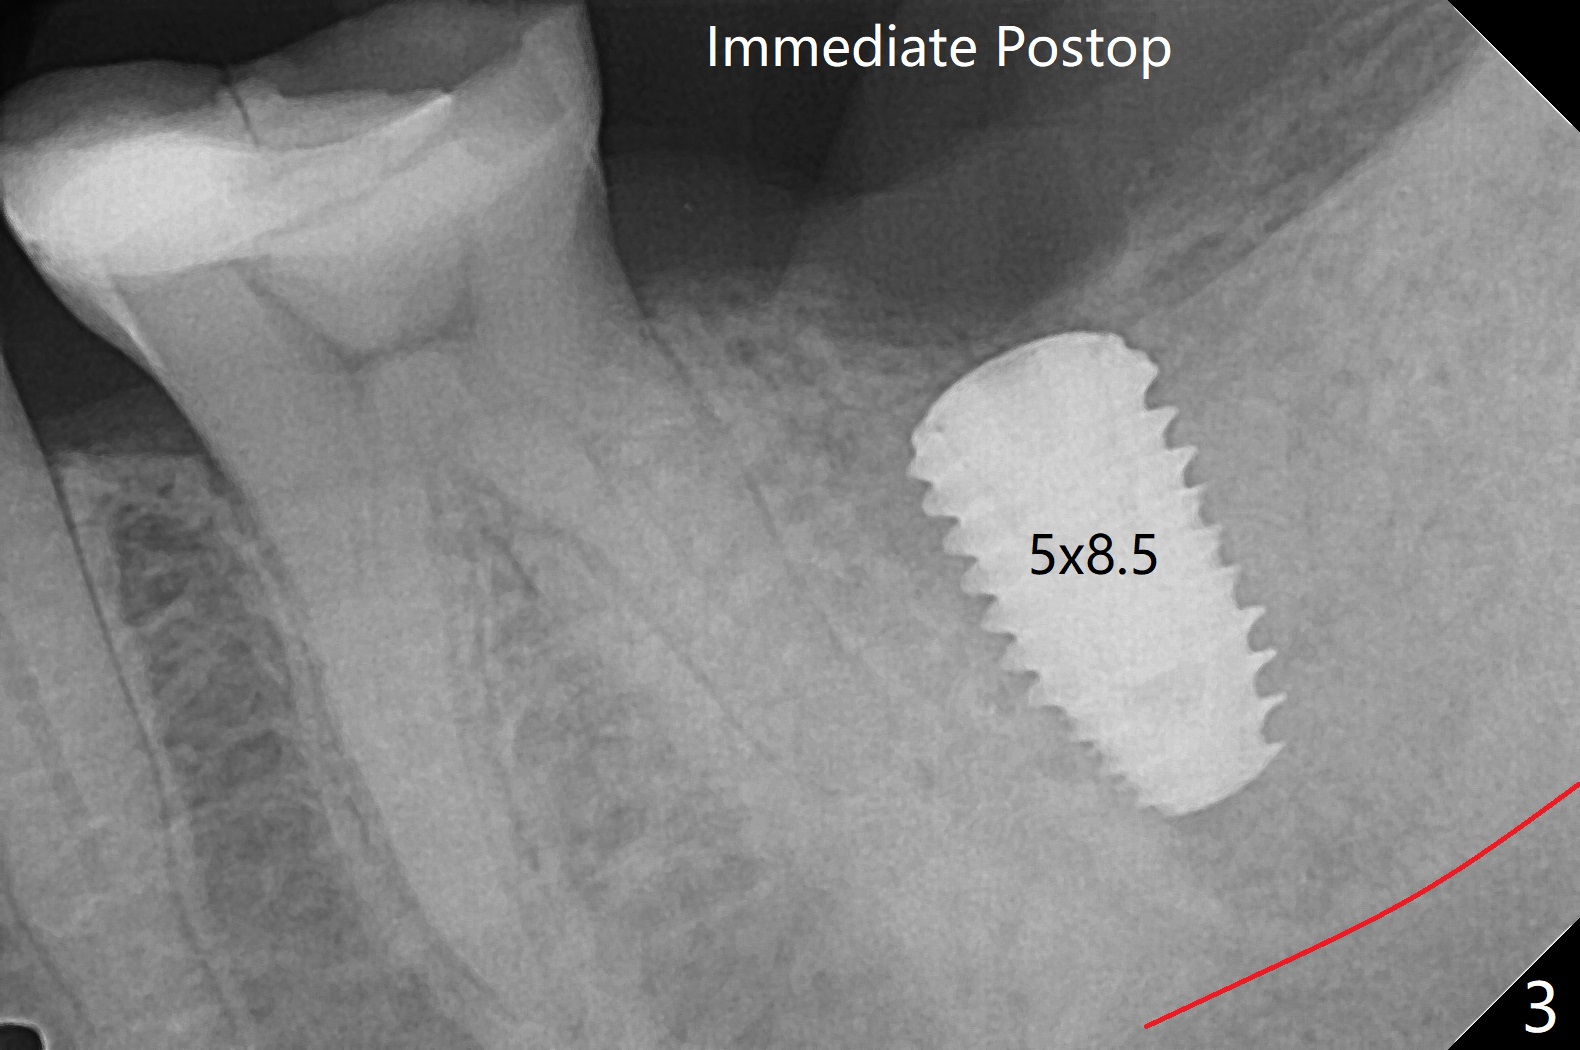

今天手术病人57岁,女,拔除左下第二磨牙后,左侧颞颌关节症状加剧,病人坚信植牙是解决途径,愿意配合。导航取模后,推荐night guard,不接受,但是她开始服用肌肉松弛剂(Cyclobenzaprine (Flexeril)),晚上睡觉好,但是她认为药物对张口度没有帮助。尽管如此,她虽然胆小,还是勇敢回来植牙。其实取模前并没有测量张口度,但是感觉没什么问题。术前测量25 毫米(图一),据说45毫米才能使用导航,抱着车到山前必有路想法,就踏上愉快行程,其实病人后牙特别短,后牙上下颌垂直距离还够,所以第一个钻头没问题,一路顺风。当植体与driver结合后,就是不能插入导板。当取下导板,将三者一起放入口腔,植体却掉入口腔,快进入咽腔。经过反复尝试,安全步骤是:首先徒手初步植入植体,然后将导板,driver和扳手(torque wrench)一起放入口腔(图二),反复确定导板和driver就位,最后使用扳手,将植体植入巧好的深度(图三)。总之,问题都有解决办法。

术前CT(图四):S:中隔。骨质密度低,拔牙时没植骨。植体容易进入近中牙槽窝。植牙设计:主要植入近中窝(图五),但是实际更近中。由于扭力低(骨质密度低),使用愈合螺帽,放置自体骨和胶原膜(C,GEM Cap),用牙周胶水固定(蓝色,图六)。胶原膜术后九天好像仍在原位(图七)。术后3个月牙槽嵴粘膜愈合正常,翻瓣后必须用钻头去除愈合螺帽冠方骨质,植体周围骨质密度增加(图八)。修复基台仿佛没有与牙槽嵴接触(图九)。调整基台高度后,取模。最后使用树脂水门汀。